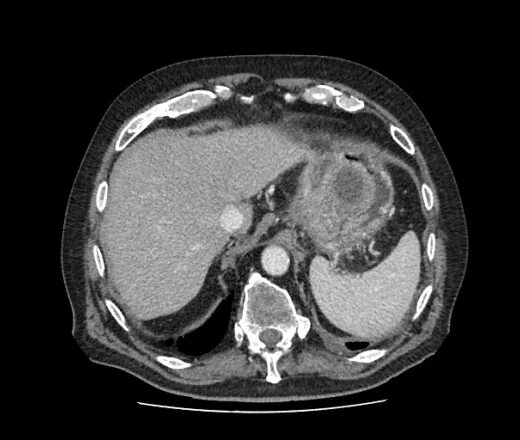

Инфильтрация паранефральной клетчатки на кт. параколитическая клетчатка кт. парапанкреатическая клетчатка инфильтрирована. перипанкреатический инфильтрат.Кт при остром панкреатите. парапанкреатическая клетчатка. кт диагностика панкреатита. острый отечный панкреатит кт.Парапанкреатическая клетчатка. поддиафрагмальное пространство. внебрюшинное поддиафрагмальное пространство. парапанкреатическая клетчатка инфильтрирована.Парапанкреатическая клетчатка что это значитКлетчатка анатомия. понятие о клетчатке в анатомии. основы клинической анатомии. клетчатка понятие.Парапанкреатическая клетчатка что это значитПарапанкреатическая клетчатка. парапанкреатическая клетчатка инфильтрирована. парапанкреатическая инфильтрация. парапанкреатическая клетчатка дифференцирована.Парапанкреатическая клетчатка что это значитПарапанкреатическая клетчатка что это значитХронический панкреатит на кт. парапанкреатическая клетчатка на кт. кт поджелудочной железы. поджелудочная железа на рентгенограмме.Парапанкреатическая клетчатка что это значитПарапанкреатическая клетчатка что это значитПарапанкреатический инфильтрат. парапанкреатическая клетчатка дифференцирована.Парапанкреатическая клетчатка что это значитПарапанкреатическая клетчатка что это значитПарапанкреатическая клетчатка поджелудочной железы. отек парапанкреатической клетчатки. парапанкреатическая инфильтрация. острый деструктивный панкреатит кт.Парапанкреатическая клетчатка что это значитПарапанкреатическая клетчатка что это значитПарапанкреатическая клетчатка что это значитПарапанкреатическая клетчатка что это значитПарапанкреатическая клетчатка что это значитПарапанкреатический инфильтрат. перипанкреатический инфильтрат. парапанкреатическая псевдокиста на кт.Парапанкреатическая клетчатка что это значитПарапанкреатическая клетчатка что это значитПарапанкреатическая клетчатка что это значитПарапанкреатическая клетчатка что это значитПарапанкреатическая клетчатка что это значитПарапанкреатическая клетчатка что это значитПарапанкреатическая клетчатка что это значитПарапанкреатическая клетчатка что это значитПарапанкреатическая клетчатка что это значитПарапанкреатическая клетчатка поджелудочной железы. перипанкреатический инфильтрат. осложнения острого панкреатита презентация. перипанкреатическая клетчатка.Парапанкреатическая клетчатка что это значитКисты и свищи поджелудочной железы. инфильтрация парапанкреатической клетчатки. истинные кисты поджелудочной железы классификация. парапанкреатическая клетчатка поджелудочной железы.Парапанкреатическая клетчатка что это значитПарапанкреатическая клетчатка что это значитПарапанкреатическая клетчатка что это значитПарапанкреатическая клетчатка что это значитПарапанкреатическая клетчатка что это значитПарапанкреатическая клетчатка что это значит